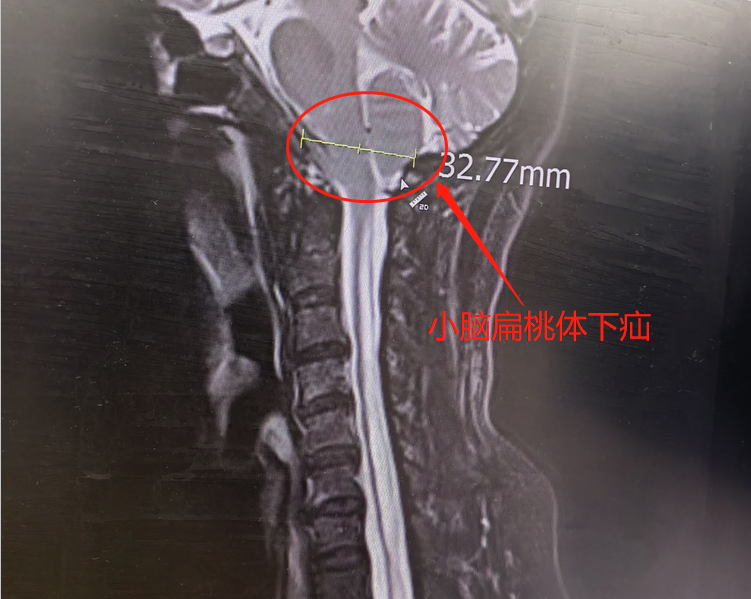

在朋友推荐下,胡大姐联系到大兴神经外科贾栋主任。通过磁共振检查,胡大姐被确诊为小脑扁桃体下疝畸形伴脊髓空洞症。

通俗地讲,就是脑子「出轨」跑到脖子,从而压迫了脊髓。